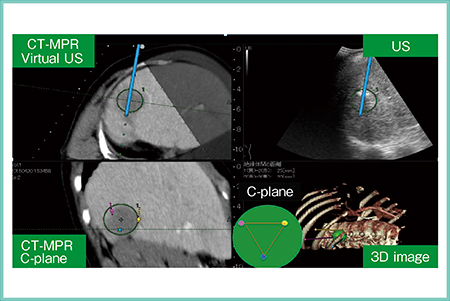

症例1は,70歳,女性。肝S6に3.4cmの肝細胞がんの再発が認められ,肝動脈化学塞栓療法(TACE)併用にてバイポーラ4cm針3本によるRFAを施行した。C-plane画像にて電極針の穿刺位置を正三角形状に設定すると,それがCT-MPR画像(Virtual US),超音波画像および3D image上に黄色,赤,青のラインで表示される(図2)。これにより,電極針相互の位置関係を容易に把握可能であった。治療後のCTでは十分なマージンが確認できた。

図2 症例1:肝細胞がん再発症例へのバイポーラRFA